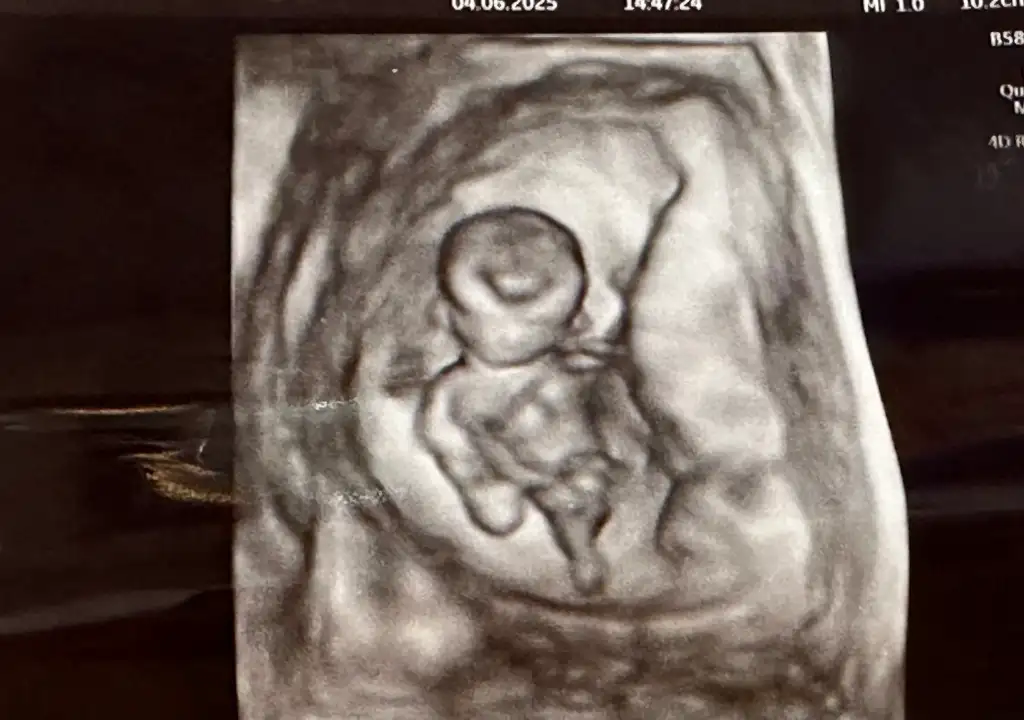

Bana da bakar mısınız lütfen biri 9 haftalık biri 6 haftalık karından ultrasonKese şekline göre erkek bence. Sağlıkla kucağınıza alın

Banada bakar mısnız lütfennnn çok merak ediyorum biri 9 haftalık biri 6 haftalık ultrason karından

Nuba göre ankıyormusunuz acaba?Bariz görünüyor kız diyorum![]()

Erkek bence. Sağlıkla kucağınıza alınBana da bakar mısınız lütfen biri 9 haftalık biri 6 haftalık karından ultraso

Tahmin edebilirmisiniz rica etsemErkek bence. Sağlıkla kucağınıza alın

Sanırım erkek sizinkiTahmin edebilirmisiniz rica etsem